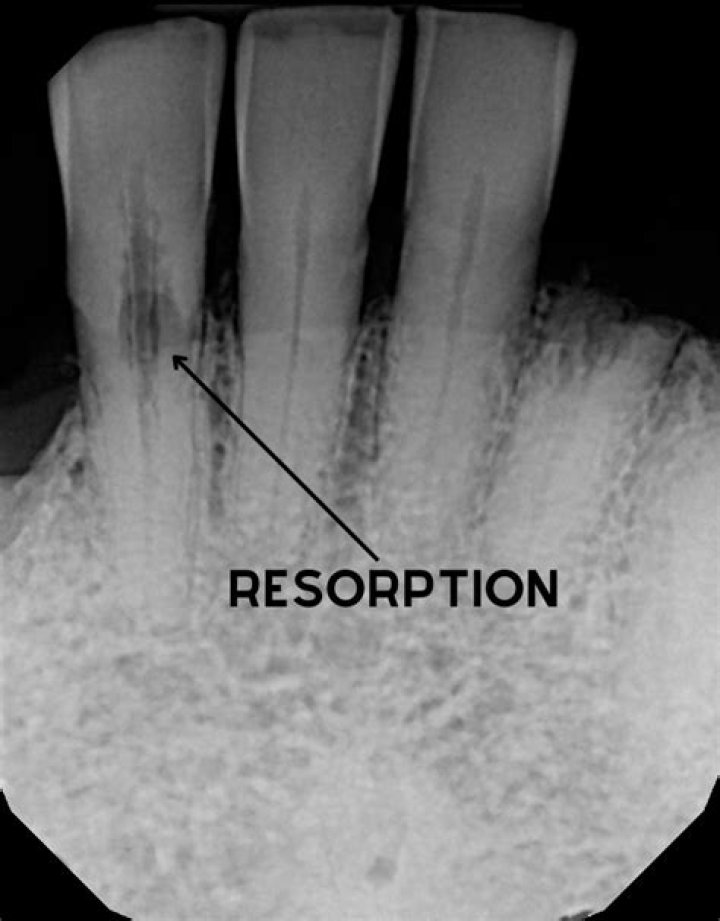

How common is internal resorption

Internal resorption (IR) is a relatively rare occurrence, and most cases follow injury to pulp tissue, such as physical trauma or caries-related pulpitis. The condition is more frequently observed in male than in female subjects.

How is tooth resorption diagnosed?

The diagnosis of internal resorption is made through a combination of clinical and radiographic findings. For internal resorption to occur, some vital pulp tissue must be present. Pulp test (electric, cold, heat) results are suggestive of tooth vitality.